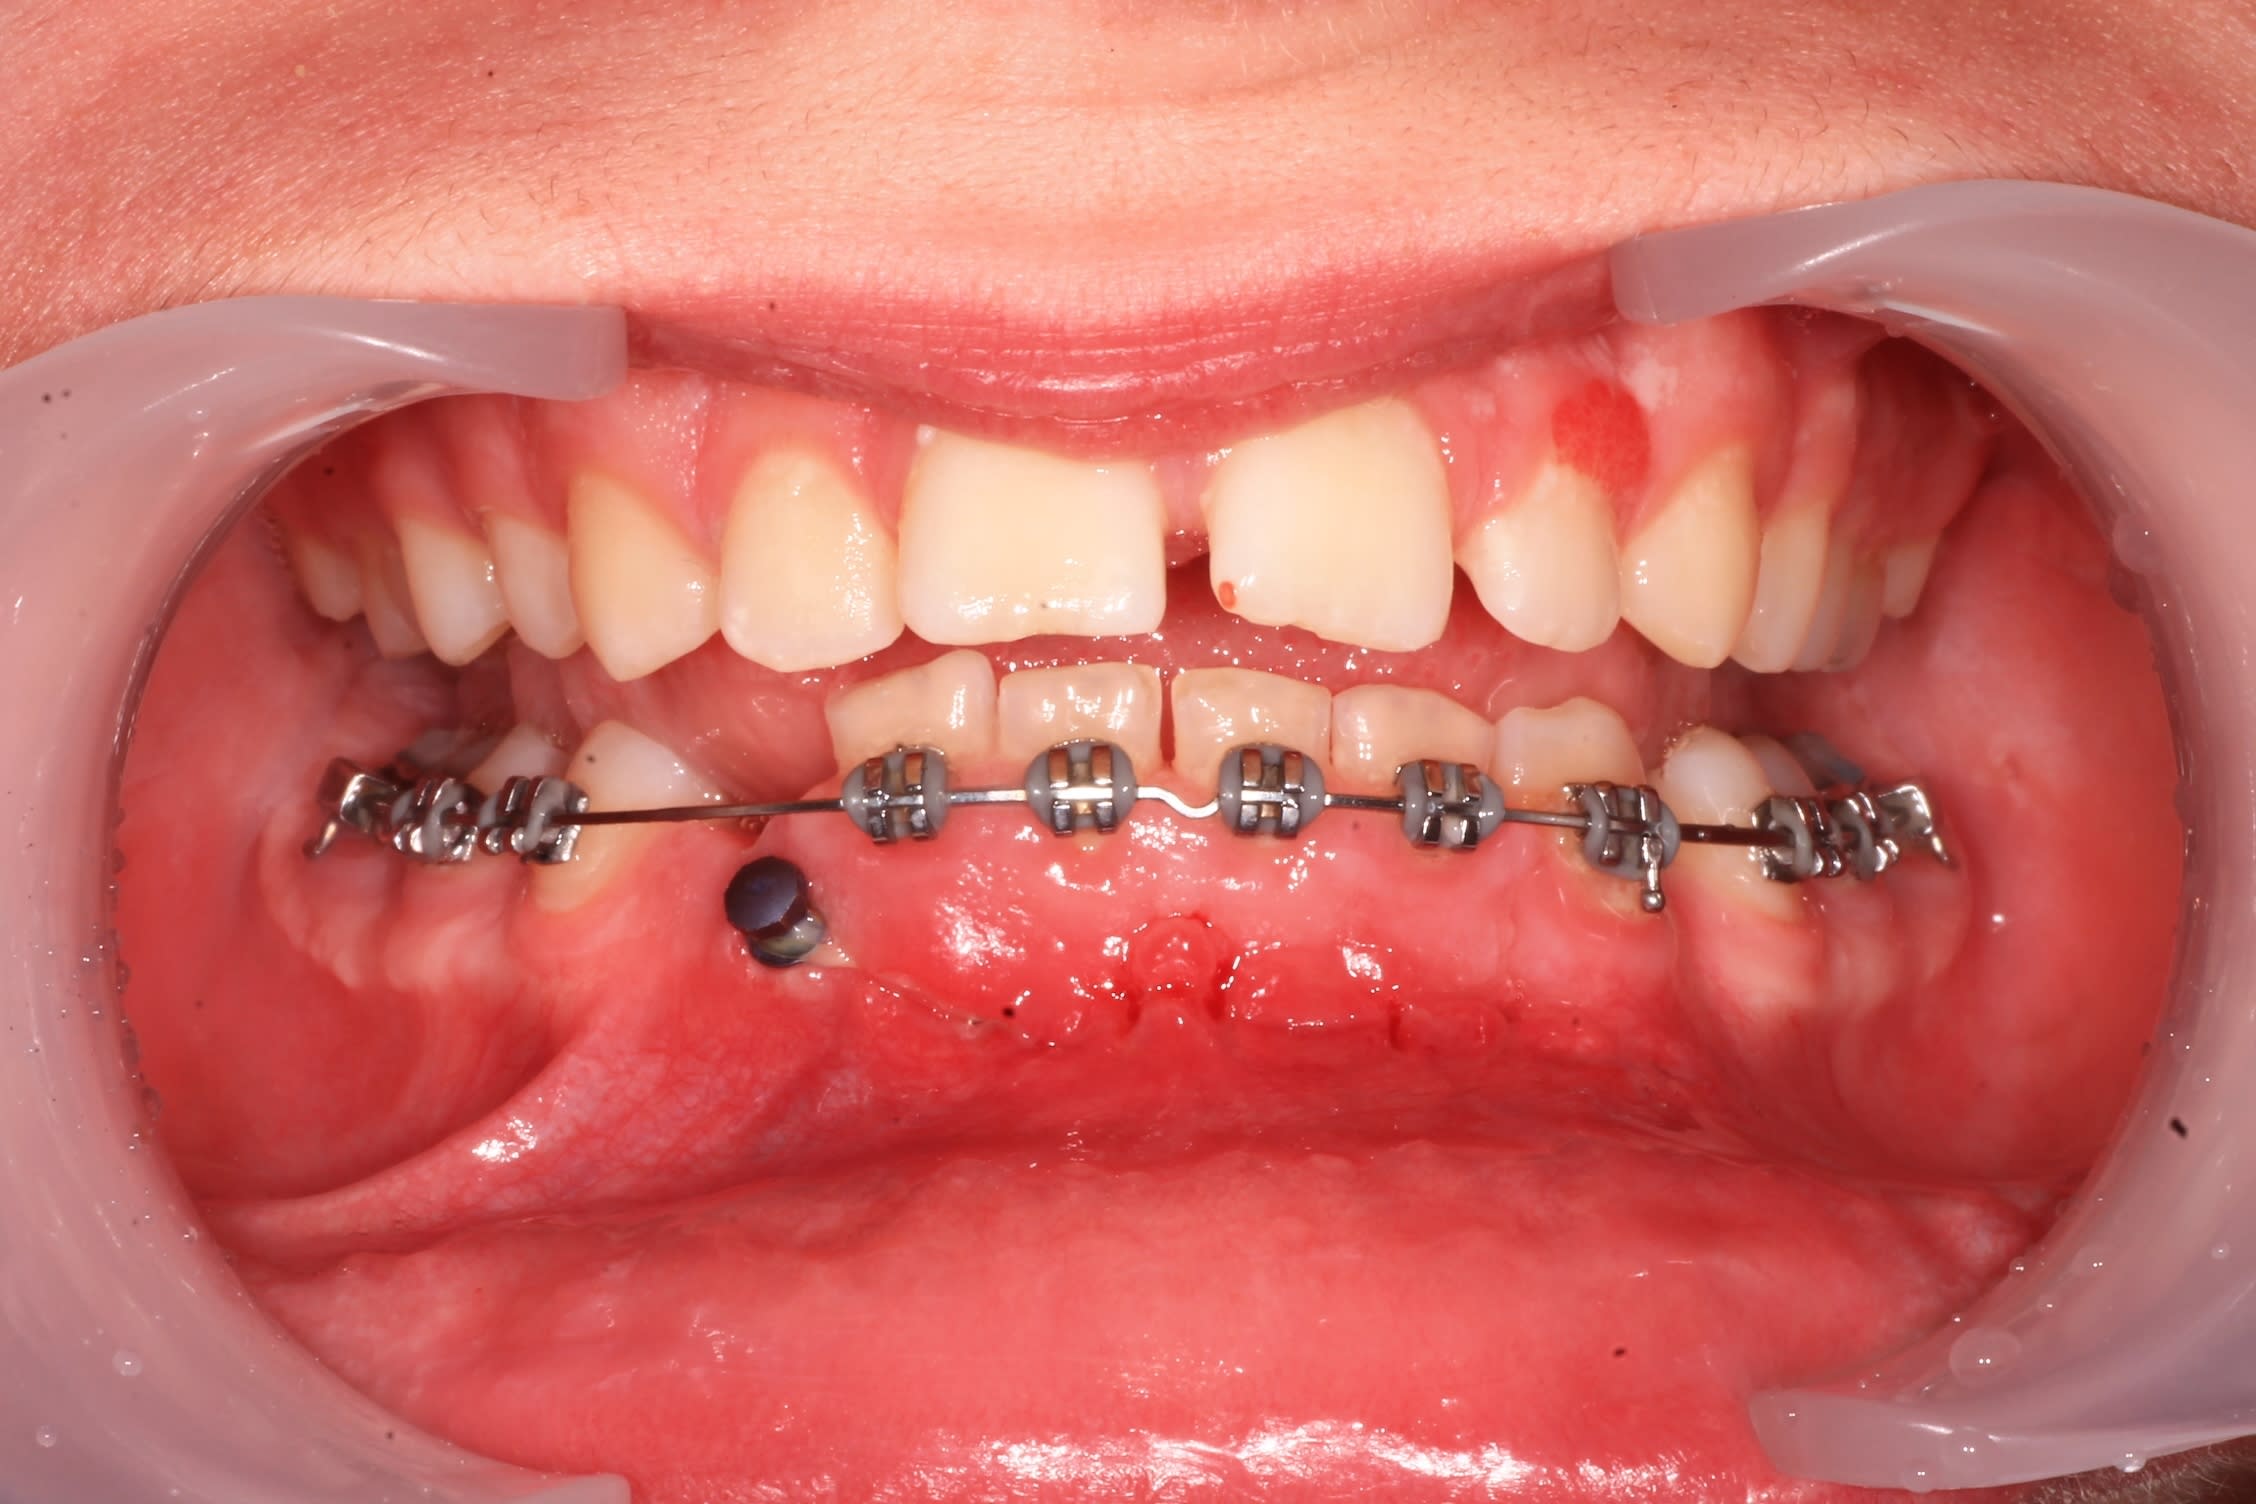

j'ai posé les brackets ce matin. Bonne idée , la minivis, cela évitera de mésialer 46.

Voici un exemple de traction de canine incluse inférieure. Il faut absolument laisser les incisives inférieures totalement libres pour qu'elles puissent un peu se déplacer spontanément si nécessaire.

La supériorité du CT8 sur n'importe quel autre ancrage pour tracter les canines incluses tient en particulier à sa longueur qui permet des forces légères (25g), avec une grande amplitude de mouvement en direction contrôlée. Prévois bien un retour du fil suffisamment long après sa pliure au niveau de la ligature pour avoir de la marge. Tu pourras alors le déplier et le replier différemment en cours de traitement si tu veux, un moment donné, modifier la direction de la force. On a en effet toujours tendance à le couper trop court.

Ct8 1 43 incluse rlrvlu - Eugenol

l'arcade est baguée, et j'ai mis une minivis, qui , comme je le pensais, provoque l'enfouissement de la chaînette dans la gencive :(

Mon patient sort du cab a l'instant, avec un CT8 tout neuf.

La traction avec la chainette sur minivis avait deja initié le travail.

Canine incluse3 crququ - Eugenol

Img 8978 2 vjmg9j - Eugenol

C'est assurément un beau fil et une belle boucle, mais es-tu sûr que tes vis vont tenir ? Elles me paraissent bien hautes par rapport à la ligne oblique externe où on les place habituellement.